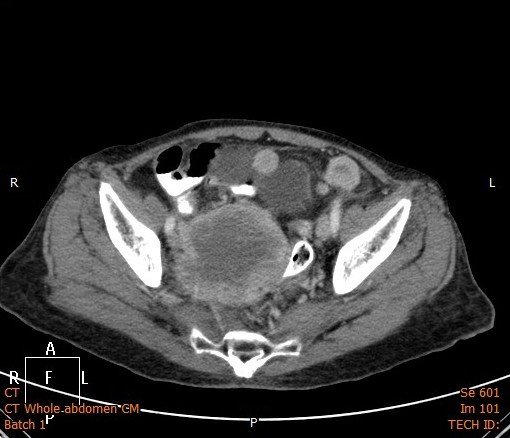

Answer : B. Abdominal/Pelvic mass

• Occasionally masses of the pelvis are visible on an abdominal X-ray.

• If large, masses of the pelvis may extend into the abdomen and displace bowel.

• Investigation with ultrasound and/or CT is required for assessment of a suspected abdominal mass.

Key points : Pelvic masses can displace bowel upwards

Abdominal CT images